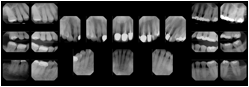

1. A patient in rural Canada visits a general ophthalmologist and is found to have diabetic macular edema. The general ophthalmologist would like to discuss the case with a retina specialist before performing laser surgery. A fluorescein angiogram is done with multiple retinal images taken in a timed series after an intravenous injection. The images along with a Structured Display are shared via a Health Information Exchange with a retina specialist in Calgary, who opens them using his Ophthalmology EMR software and consults via phone with the general ophthalmologist. Both physicians view the images in the same layout so the retina specialist can provide accurate guidance for treating the patient.

2. A patient in rural Iowa visits his primary care physician for management of diabetes. Three non-mydriatic (patient's eyes are not dilated) photographs are taken of the back of each eye, and forwarded electronically along with a Structured Display to an ophthalmologist in Iowa City. The ophthalmologist reads the photos in an agreed upon layout so there is no mistake about what portion of which eye is being viewed. The ophthalmologist is able to tell the primary care physician that his patient does not need to come to Iowa City for face to face ophthalmologic care, but that there is a particular view of the left eye that should be photographed again in 6 months.

Ophthalmic Retinal Study Structured Display

Figure OO-3. Ophthalmic Retinal Study Structured Display

3. A patient in rural Minnesota experiences sudden vision loss and goes to a general ophthalmologist, who acquires OCT images and forwards them electronically along with a Structured Display to a retina specialist six travel hours away. The retina specialist is able to view the images in the standard layout that he is comfortable with, and to confirm that the patient has a choroidal neovascular membrane. He determines that is would be worthwhile for the patient to travel for treatment.

OCT Retinal Study with Cross Section and Navigation Structured Display

Figure OO-4. OCT Retinal Study with Cross Section and Navigation Structured Display